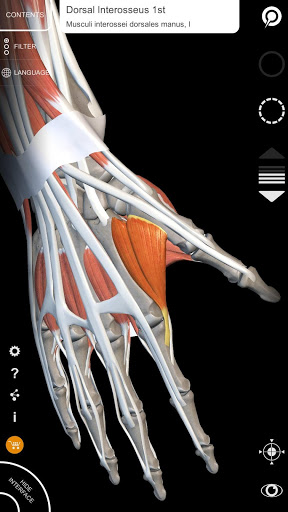

"Anatomy 3D Atlas" дозволяє легко та інтерактивно вивчати анатомію людини.

Завдяки простому та інтуїтивно зрозумілому інтерфейсу можна спостерігати кожну анатомічну структуру під будь-яким кутом.

Анатомічні 3D-моделі особливо деталізовані та мають текстури з роздільною здатністю до 4k.

АНАТОМІЧНІ 3D МОДЕЛІ

• Кістково-м’язова система

• Візуалізація м’язів через рівні шарів від поверхневих донизу до найглибших

• Вибравши модель або шпильку, з’явиться відповідний анатомічний термін

• Опис м’язів: походження, приєднання, іннервація та дія